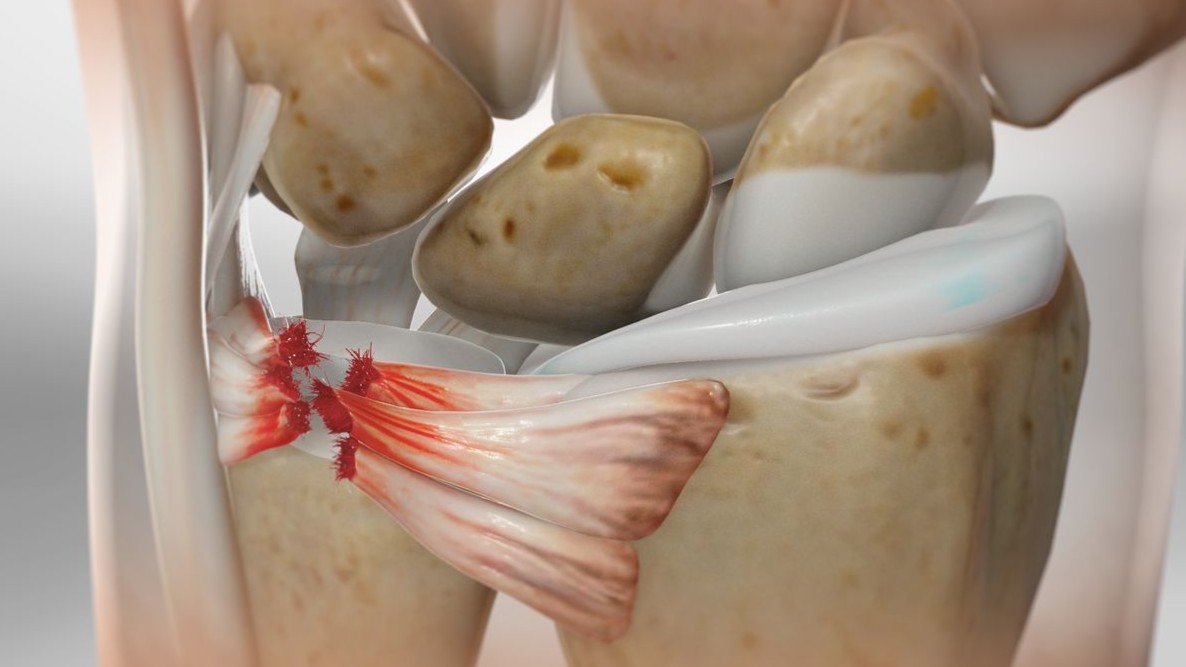

Narayana Kurup JK, Shah HH. A rare case of rubber band syndrome of wrist with distal radius and ulna fracture. J Orthop. 2020;20:60-62.

pubmed.ncbi.nlm.nih.gov/32042231